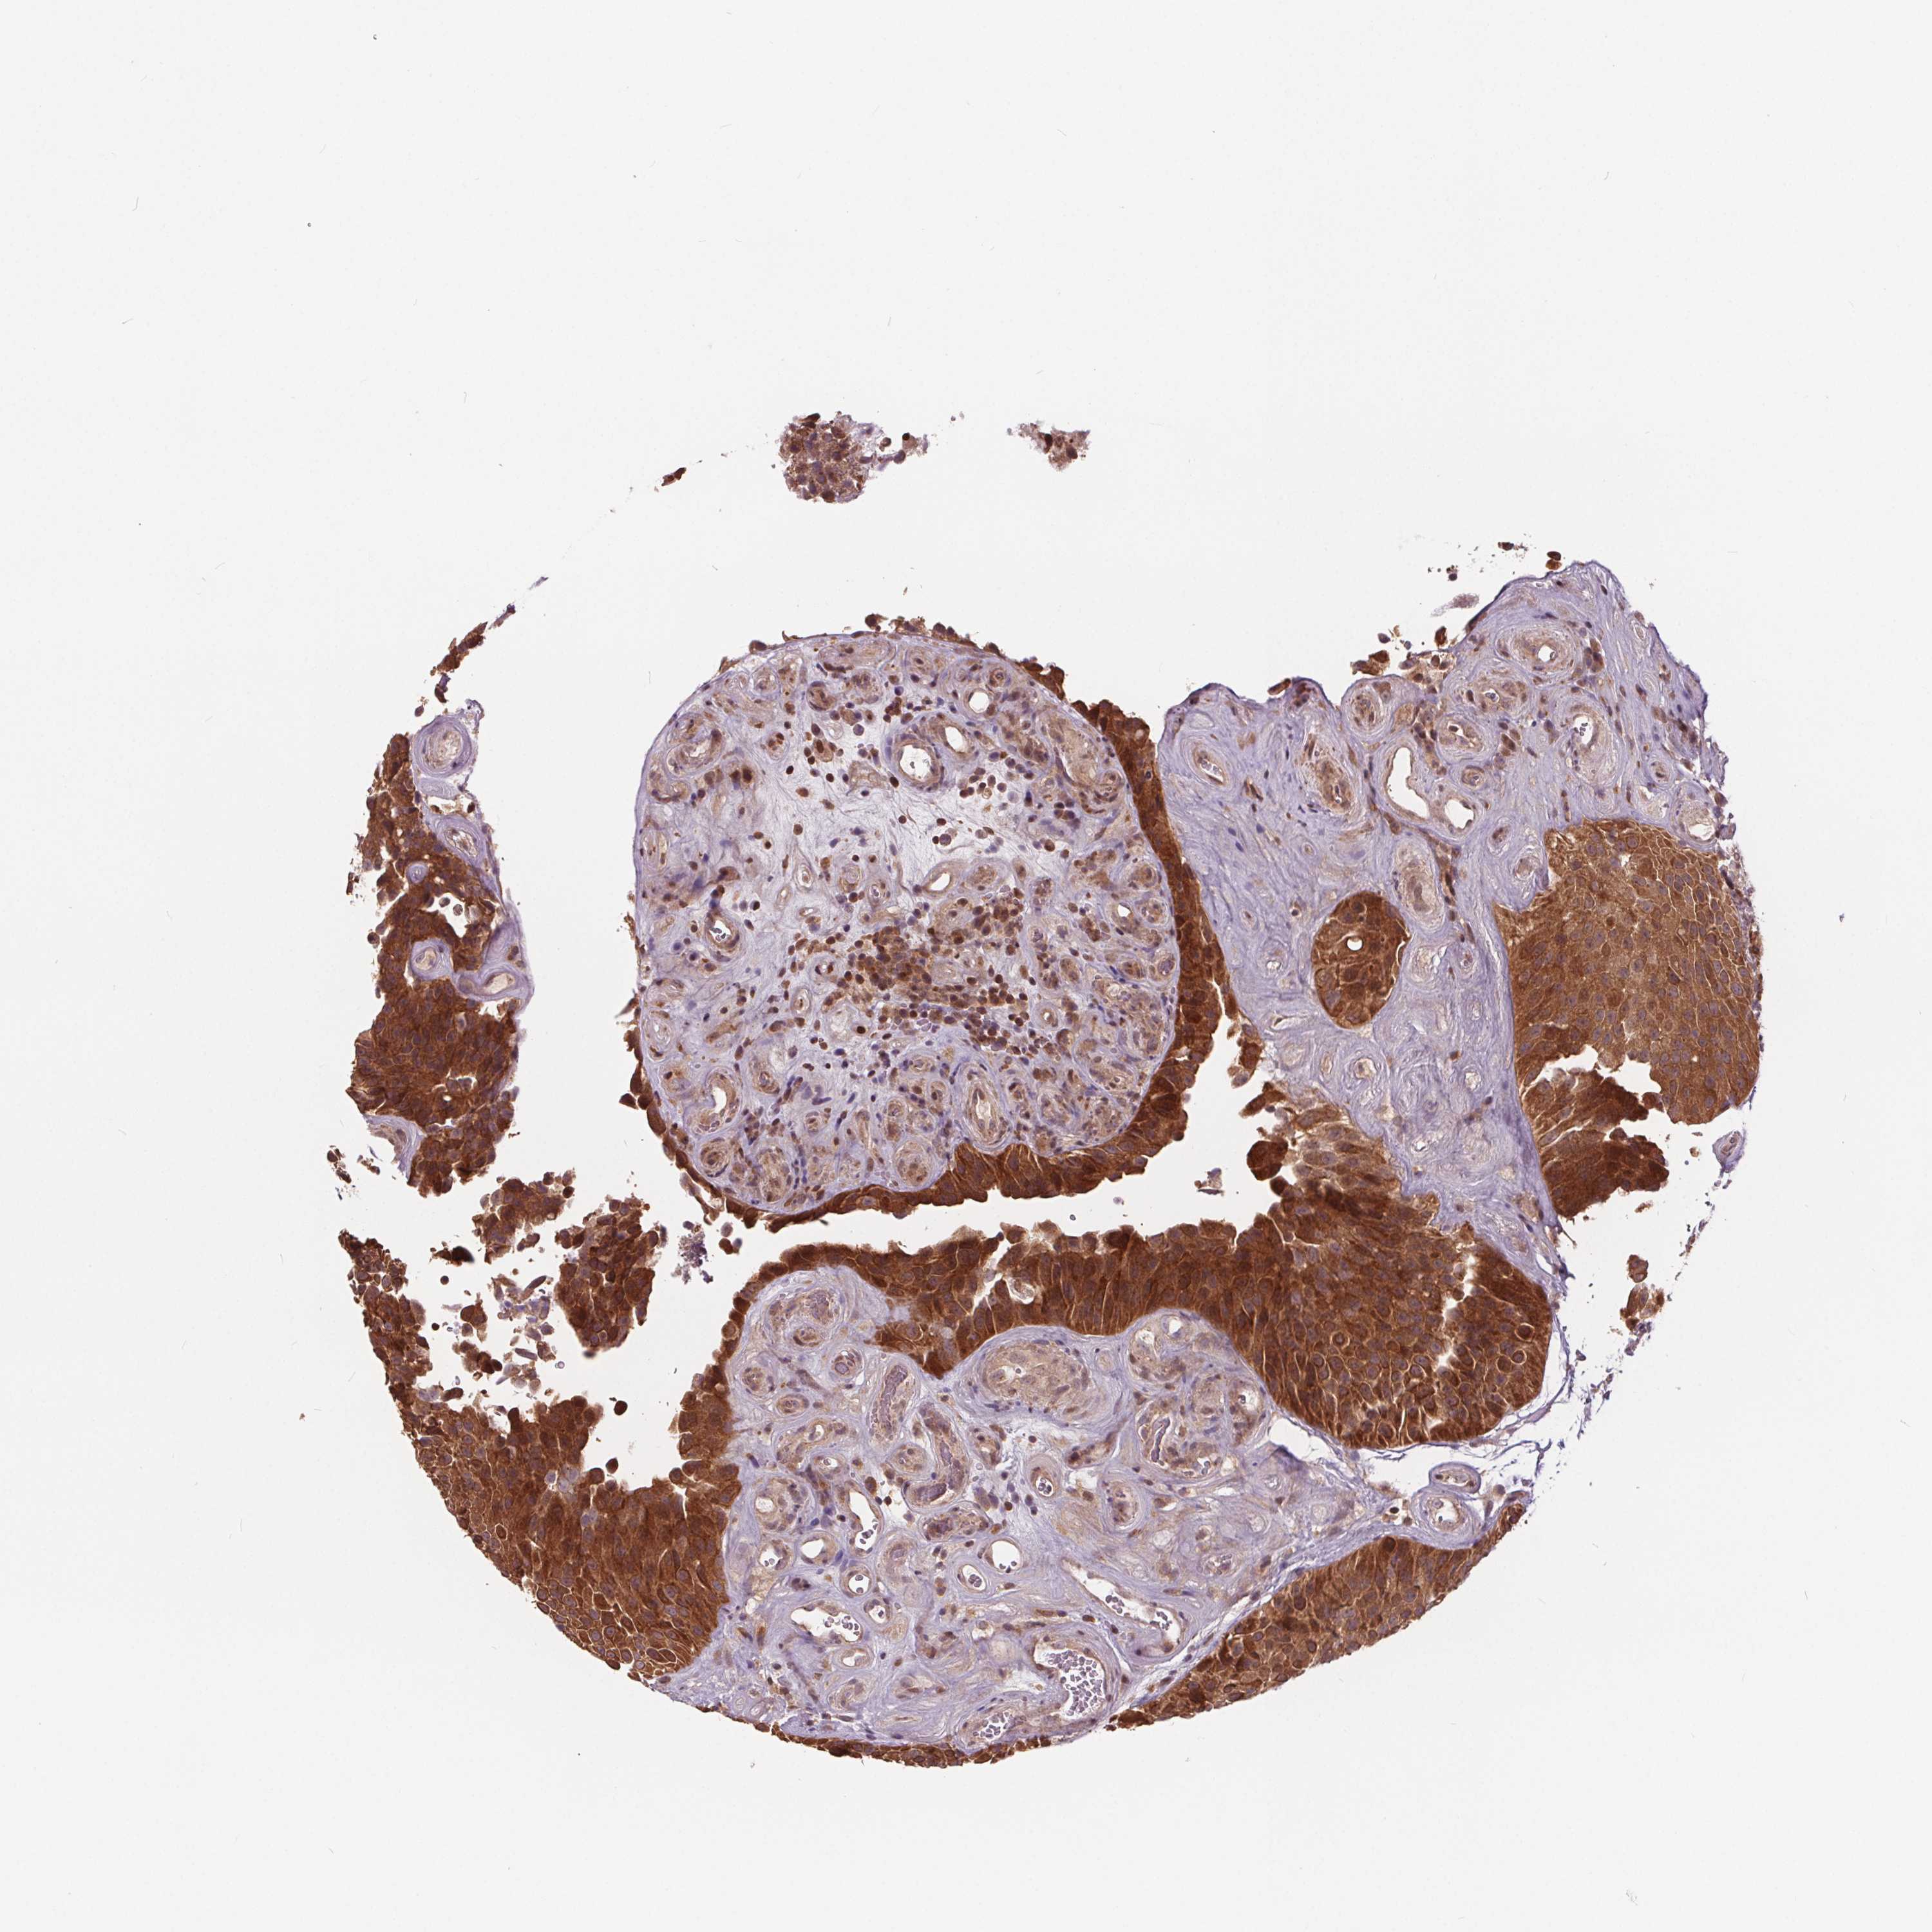

UROTHELIAL CANCER - Protein expressioni

A mouse-over function shows sample information and annotation data. Click on an image to view it in a full screen mode. Samples can be filtered based on level of antibody staining by selecting one or several of the following categories: high, medium, low and not detected. The assay and annotation is described here.

Antibody stainingi

Antibody staining in the annotated cell types in the current human tissue is reported as not detected, low, medium, or high, based on conventional immunohistochemistry profiling in selected tissues. This score is based on the combination of the staining intensity and fraction of stained cells.

Each image is clickable and will lead to virtual microscopy that enables deeper exploration of all samples and also displays staining intensity scores, fraction scores and subcellular localization as well as patient and tissue information for each sample.

Antibody HPA065302

Antibody CAB069903

Staining

High

Medium

Low

Not detected

Intensity

Strong

Moderate

Weak

Negative

Quantity

>75%

75%-25%

<25%

None

Location

Nuclear

Cytoplasmic/membranous

Cytoplasmic/membranous,nuclear

Urothelial carcinoma, High grade

Urothelial carcinoma, Low grade